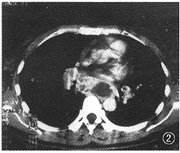

1个月后复查胸片见左肺病灶部分吸收。4个月后复查胸片见左肺病灶吸收,肺门扩大,纵隔增宽。胸部CT扫描:纵隔淋巴结肿大伴中心坏死。两肺见多发性小结节影,左下肺呈间质性改变(图2,3)。纤维支气管镜见左右主支气管呈外压性改变。活检病理报告:肉芽肿性炎症。患者再次入院时除低热、咳嗽外还诉左上腹不适。B超检查示脾肿大,脾内见多发异常回声灶。腹部CT平扫:肝未见异常,脾脏明显肿大,密度不匀,其中见多发性大小不一、边缘模糊的低密度灶(图4)。先后作2次脾穿刺活检。病理报告:肉芽肿性炎症,何杰金病不能排除。此时开始不规则服用强的松治疗,但发热一直不退,患者自动出院。

图2,3 发病4个月肺CT检查示纵隔淋巴结肿大、并坏死形成,双肺结节性病变伴左下肺间质改变